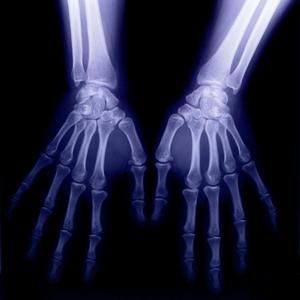

人體X光圖片 軔致輻射:當高速電子流撞擊陽極靶受到制動時,電子在原子核的強電場作用下,速度的量值和方向都發生急劇的變化,一部分動能轉化為光子的能量而輻射出去,這就是軔致輻射。

X射線診斷 醫用診斷X線機:醫用X線機醫學上常用作輔助檢查方法之一。臨床上常用的x線檢查方法有透視和攝片兩種。透視較經濟、方便,並可隨意變動受檢部位作多方面的觀察,但不能留下客觀的記錄,也不易分辨細節。攝片能使受檢部位結構清晰地顯示於x線片上,並可作為客觀記錄長期保存,以便在需要時隨時加以研究或在複查時作比較。必要時還可作x線特殊檢查,如斷層攝影、記波攝影以及造影檢查等。選擇何種x線檢查方法,必須根據受檢查的具體情況,從解決疾病(尤其是骨科疾病)的要求和臨床需要而定。x線檢查僅是臨床輔助診斷方法之一。